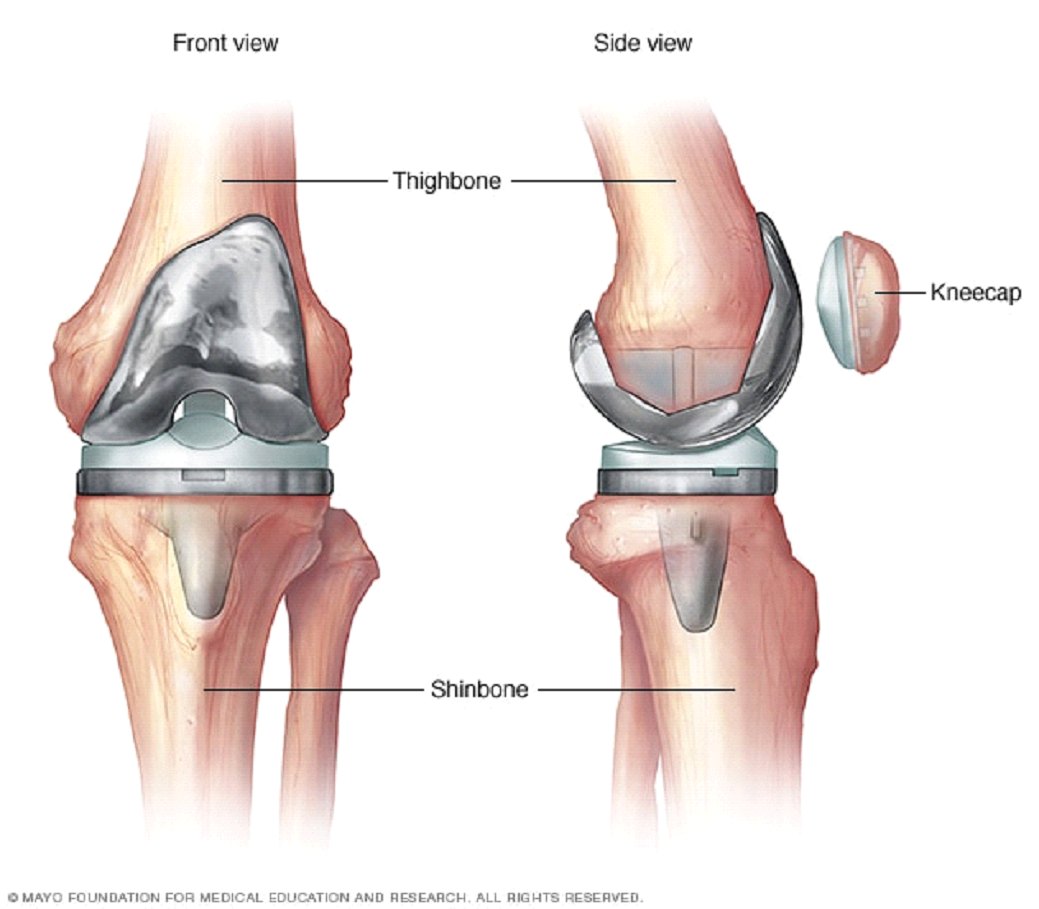

The knee is a complex joint formed by the thigh bone (femur), shin bone (tibia), and knee cap (patella). Cartilage covers the ends of the bones to help smooth, pain-free movement. Menisci (medial and lateral) act as shock absorbers and provide stability. Ligaments (ACL, PCL, MCL, LCL) hold the joint together.

Options: Total or partial knee replacement. Arthroscopy (keyhole surgery) is not recommended for OA alone.